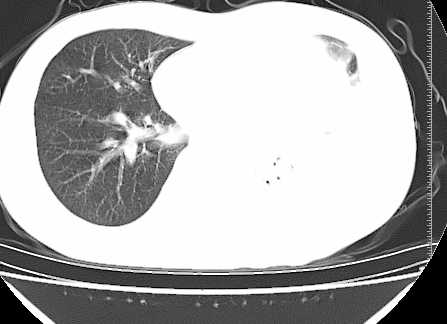

二周前患者无明显诱因出现咳嗽,多为刺激性干嗽,无咯血,伴心悸,低热,夜间无明显盗汗,消瘦明显

年龄?左侧胸腔中量积液,左下肺见有较多斑片状和大片状影,伴有支气管充气征,考虑:1、左下肺炎;2、结核。肿瘤可以基本排除。

考虑:1、左下肺结核左侧胸腔中量积液,心包积液纵隔肿大淋巴结.

考虑:1、左侧中量胸腔积液伴左肺下叶肺膨胀不全、炎症。

2、心包积液。

左下肺见有较多斑片状和大片状影,支气管通畅,左侧胸腔积液,考虑:左下肺炎伴胸腔积液

左侧中量胸腔积液伴左肺下叶肺膨胀不全、上肺外围多个小囊样腺泡样病灶。考虑化脓炎症。

心包积液没有,纵隔积液。

纵隔肿大淋巴结不明显。

左肺舌叶及下叶见斑片状,大片状高密度影并相应处胸膜及心包不规则增厚,左肺下叶膨胀不全。右肺未见异常,双肺段以上支气管通畅。纵隔左移,其内未见明显肿大淋巴结。左侧胸腔积液。

1.考虑:左肺化脓性炎症。2.左侧胸腔积液(中等量)。3.心包炎症。